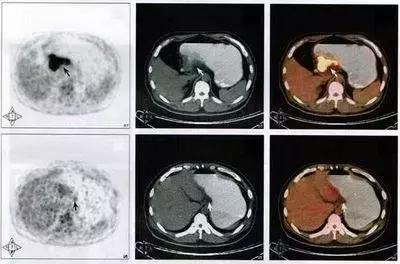

PET-CT

它又是什么鬼?

PET/CT:将PET和CT有机的结合在一起,使用同一个检查床合用一个图像工作站,PET/CT同时具有PET,CT及将PET图像与CT图像融合等功能。

PET全称为正电子发射计算机断层显像(positron emission tomography PET),是反映病变的基因、分子、代谢及功能状态的显像设备。它是利用正电子核素标记葡萄糖等人体代谢物作为显像剂,通过病灶对显像剂的摄取来反映其代谢变化,从而为临床提供疾病的生物代谢信息。是当今生命科学、医学影像技术发展的新里程碑。

PET看的是组织的代谢。也就是说,通过异常的代谢来判断全身上下是否有病变,其中最敏感的要属肿瘤性病变,因为肿瘤的特点就是代谢旺盛。

但是PET也存在相当的局限性,首先就是扫描层面的问题,扫描整个人,层面相对比单独扫一个器官要粗略很多,一些细小的问题可能被忽略。然而很多良性疾病,代谢改变不大,在PET扫描的时候也不会被发现。

另外,即使看到病灶,由于扫描的精确度问题,也仅仅可以定位病灶的存在,对于其具体性质还需要进行进一步的专项扫描。在发达国家,PET广泛应用于临床,已成为肿瘤、冠心病和脑部疾病这三大威胁人类生命疾病诊断和指导治疗的最有效手段。

▲PET-CT检测影像资料